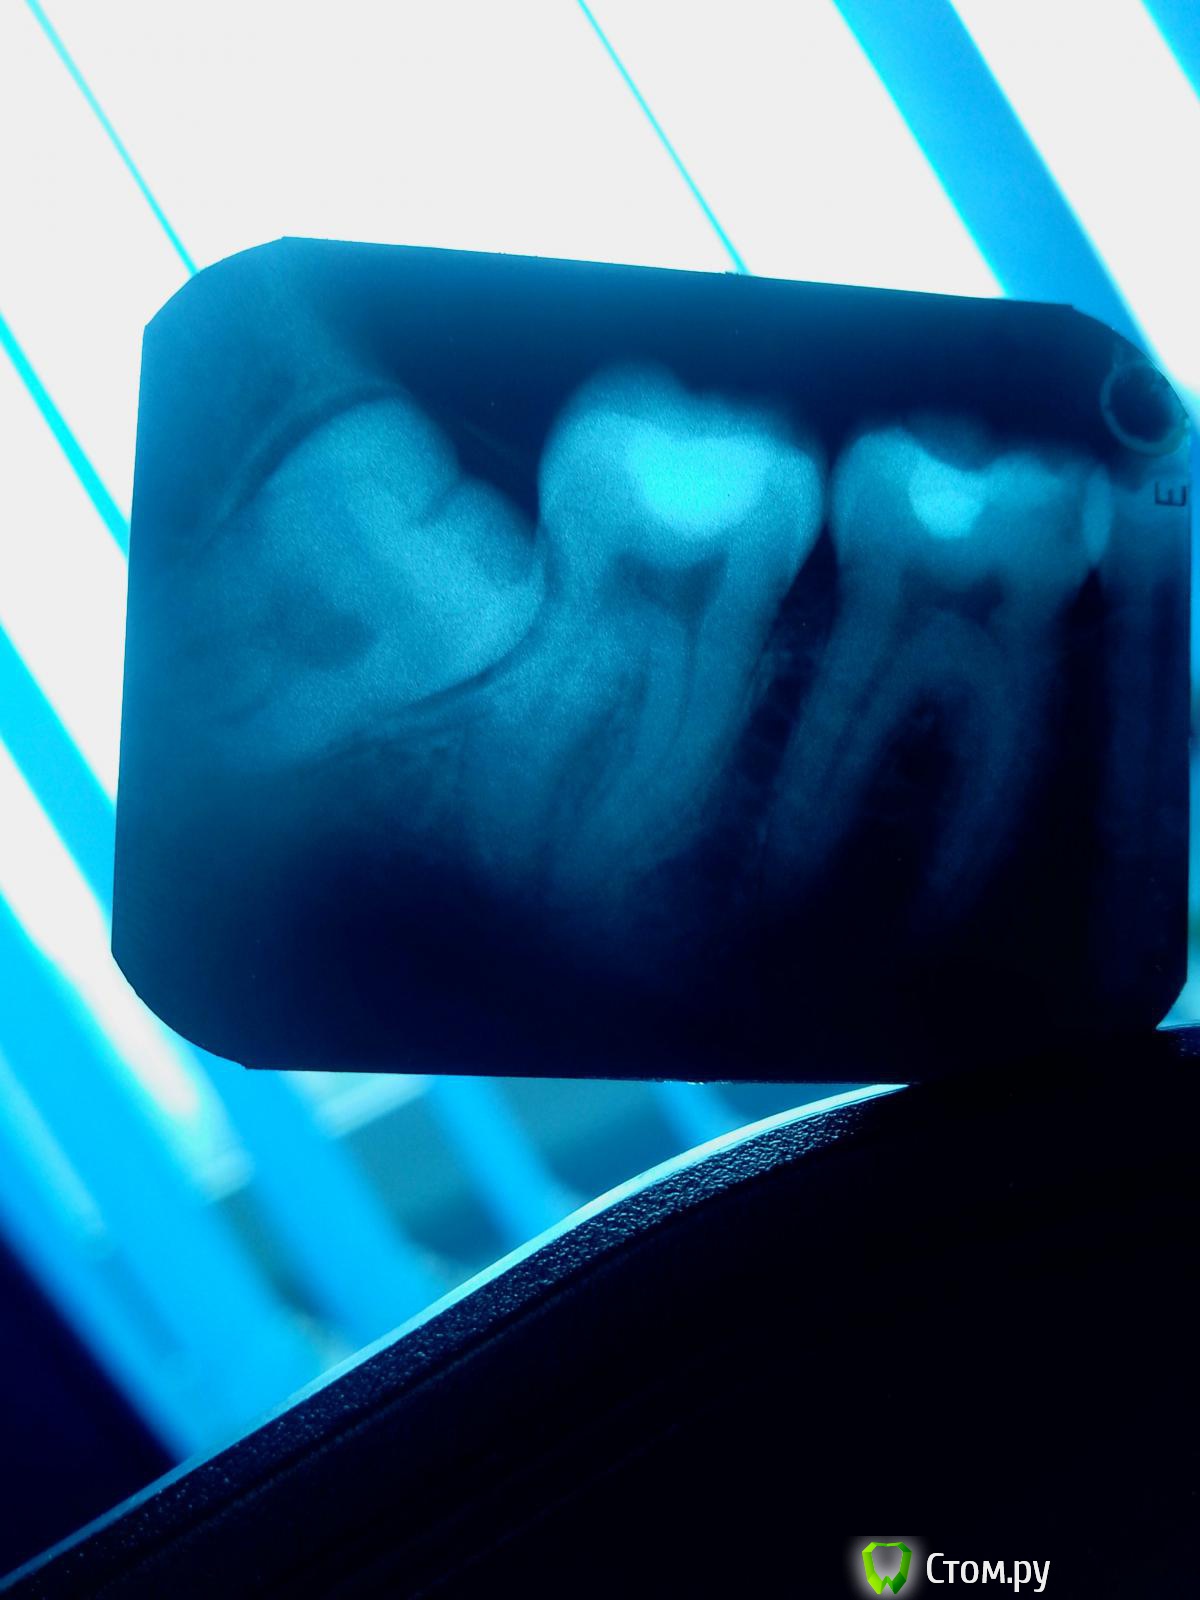

Эльzа Опубликовано 3 мая, 2014 Поделиться Опубликовано 3 мая, 2014 Добрый день, Проконсультируйте, пожалуйста, на тему удаления восьмерок. Заняться данным вопросом меня вынудила боль в нижней левой 7ке – сначала просто постоянная ноющая (довольно сильная, пила обезболивающие), через пару дней трансформировалась в острую простреливающую при даже минимальном соприкосновении 7ки с верхними зубами. Сейчас на 7ку я могу осторожно жевать и даже слегка клацать зубами, не болит. Это так сказать вводная. Теперь основное. Снимок снял подозрения о проблеме под пломбой с 7ки и обозначил необходимость удаления 8ки (даже без привязки к боли в зубе). Консультировалась с несколькими специалистами, но открытые вопросы все еще есть. А именно:Два рекомендованных хирурга (очень рекомендованных, из гос учреждений правда) назвали данное удаление сложным/очень травматичным и сориентировали на продолжительность час+, один из них даже рассматривал вопрос амбулаторного удаления.. ответы в похожих темах про 8ки настораживают – у меня вроде бы не всё так плохо и не должна данная манипуляция занимать час+, хотя я не врач конечно Уважаемые, а вы как оцениваете сложность/продолжительность данного удаления? Третий хирург, ввиду очень близкого расположения 8ки к 7ке, сказала, что болезненность 7ки может сохраниться и после удаления 8ки (теперь уже не из-за давления 8ки на 7ку, а из-за оголенных корней 7ки). В общем она порекомендовала сначала депульпировать 7ку, т.к. опасается, что эту процедуру всё равно потом придется делать. Ваше мнение? По самОй процедуре удаления – насколько я понимаю есть 2 варианта – швы или открытая лунка с какими-то там тампонами/лекарствами. В чем смысл и преимущества второго варианта - по описанию он выглядит гораздо менее "удобным"? Что предпочтительнее в моем случае? или это станет ясно по ходу дела? Мне что-то говорили про выдалбливание кости.. если честно неочень помню, в шоке была)) и могу что-то путать, можете прокомментировать – это актуально/необходимо в моем случае? Я правильно понимаю, что со второй 8кой тоже надо распрощаться? Я правильно понимаю, что мне повезло и верхних 8к у меня нет и не будет (мне 29 лет)? И последнее – что за светлые области на снимке – нижняя челюсть, с обоих сторон под 6-7ками?Большое спасибо за ответы! Ссылка на комментарий

diesel87 Опубликовано 3 мая, 2014 Поделиться Опубликовано 3 мая, 2014 Добрый вечер1. С учетом анестезии 30-40 минут максимум2. С оголенными корнями 7-ого думаю ничего страшного не произойдет, а вот кариес корня возможен, но тоже под вопросом, я бы сначала убрал явную причину (8-ку), а через неделю бы оценил ситуацию3. Я бы предпочел и предпочитаю швы, считаю надежнее4. Выдалбливание это грубо сказано) распил коронки 8-ого и может чуть косточку за ним зацепить, но главное слово то "распиливание"))5. Да6. Да, возраст уже не важен, их просто НЕТ) и не будет)7. Пальцы рентгенлаборанта)) (наслаивание других костных структур) 3 Ссылка на комментарий